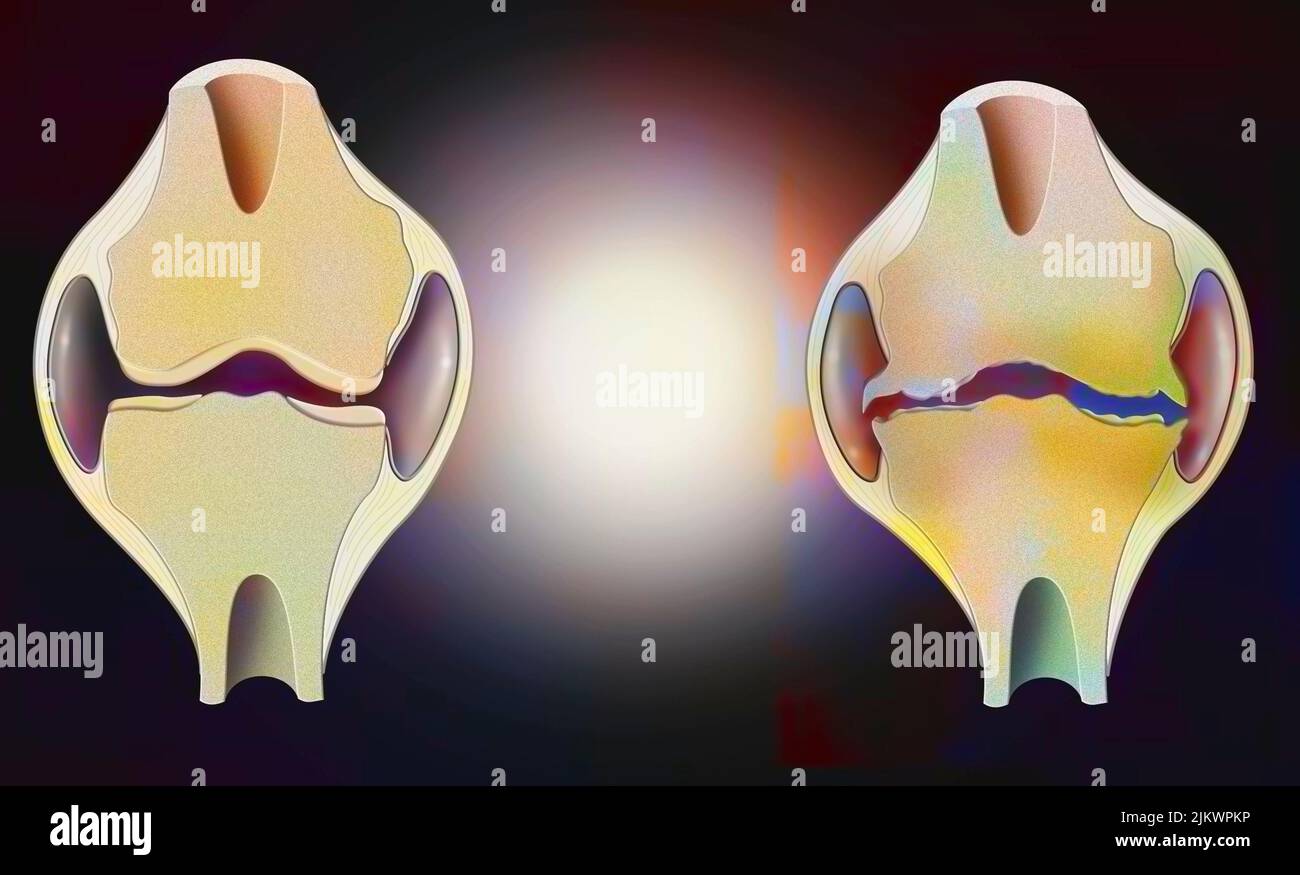

Anatomy of the joint of a healthy knee on the left, and one deformed by osteoarthritis on the right. Stock Photohttps://www.alamy.com/image-license-details/?v=1https://www.alamy.com/anatomy-of-the-joint-of-a-healthy-knee-on-the-left-and-one-deformed-by-osteoarthritis-on-the-right-image476925002.html

Anatomy of the joint of a healthy knee on the left, and one deformed by osteoarthritis on the right. Stock Photohttps://www.alamy.com/image-license-details/?v=1https://www.alamy.com/anatomy-of-the-joint-of-a-healthy-knee-on-the-left-and-one-deformed-by-osteoarthritis-on-the-right-image476925002.htmlRF2JKWPKP–Anatomy of the joint of a healthy knee on the left, and one deformed by osteoarthritis on the right.